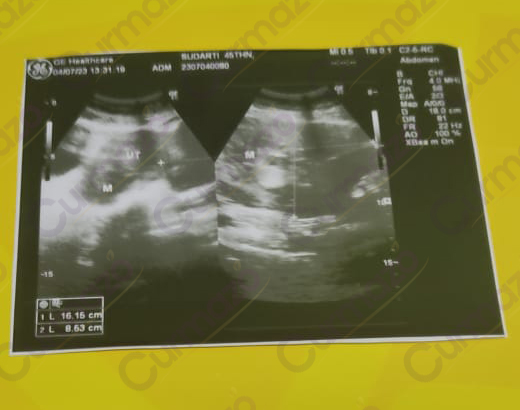

Juli 2023, saya periksa dan hasilnya ada miom 16.15 cm dan kista 5.8 cm. Sehingga disarankan operasi, namun saya menolak karena tensi tinggi dan tidak mau ambil resiko.

Suami memberitahu saya Curmazo & K-Muricata dari Facebook, karena tertarik melihat banyak yang berhasil sembuh dari kista & miom. Saat itu juga saya langsung pesan 1 paket.

Akhir Juli 2023, saya mulai rutin konsumsi Curmazo & K-Muricata.

1 bulan konsumsi, badan sudah mulai enakan. Namun saya belum ingin melakukan pemeriksaan, saya masih ingin konsumsi herbal ini.

5 September 2023, saya melakukan pemeriksaan ulang. Alhamdulillah hasilnya miom saya mengecil dari ukuran 16.15 cm menjadi 4.2 cm, saya masih rutin konsumsi sambil olahraga dan mengikuti panduan pola makan sehat dari ahli gizinya.

Juli 2024, saya melakukan pemeriksaan ulang dan miomnya dinyatakan mengecil dari 4.2 cm menjadi 3.64 cm dan kista saya hilang total. Alhamdulillah sekarang sudah bisa beraktifitas dengan nyaman & bisa membantu suami berjualan lagi. Saya masih terus konsumsi Curmazo & K-muricata agar miom hilang total.